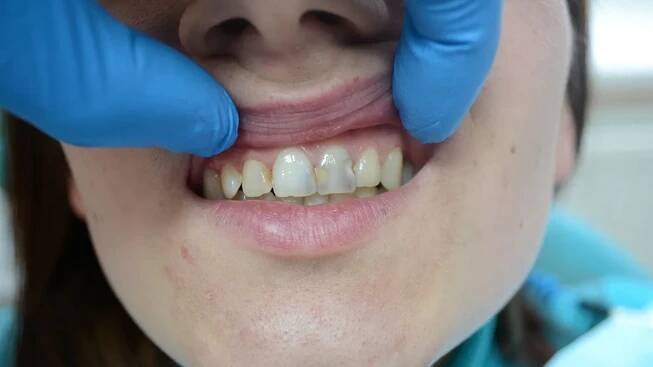

Kyretáž zubů, jinak také označováno jako deep scaling, je metoda hloubkového čištění povrchu zubních kořenů, při které se odstraňuje zubní kamen a případné zánětlivé tkáně. Jde o oškrábání a očištění stěn kořene zubu a měkkých tkání vnitřní stěny dásní, při kterém se používá nástroj zvaný kyreta. V podstatě jde o…

Kyretáž zubů je oškrábání a očištění stěn kořene zubu a měkkých tkání vnitřní stěny dásňového chobotu pomocí kyrety. Kyretáž v širším slova smyslu zahrnuje úplné odstranění zubního plaku, pevných útvarů jako je zubní kámen, zanícené tkáně…

Kyretáží zubů popisujeme očištění stěn kořene zubu a měkkých tkání dásní od zubního plaku či zubního kamene. Kyretáž zubu se používá jako metoda léčby parodontotidy.